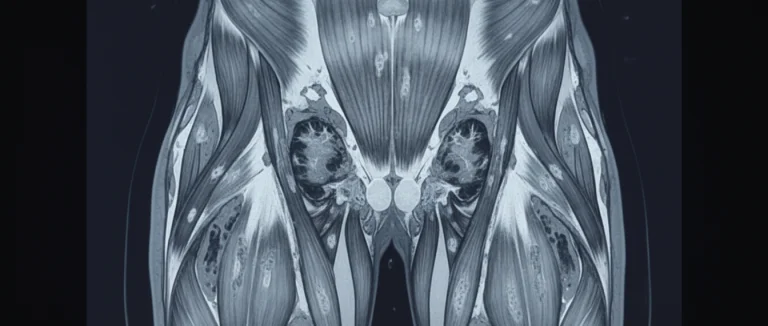

- Магнитно-резонансная томография (MRI) – визуализация структуры мышечных тканей.

Электромиография измеряет электрическую активность мышц и помогает различать нейромышечные и мышечные патологии. Магнитно‑резонансная томография визуализирует структуру мышечных тканей, выявляя зоны дегенерации и воспаления. Генетическое тестирование обнаруживает конкретные мутации, что особенно важно при наследственных дистрофиях. Анализ крови определяет уровень креатинкиназы и других ферментов, указывающих на мышечный повреждения. При необходимости проводится биопсия, позволяющая изучить гистологию ткани под микроскопом. Современные центры, такие как Лив Хоспитал, используют комбинированный подход для повышения точности диагноза.